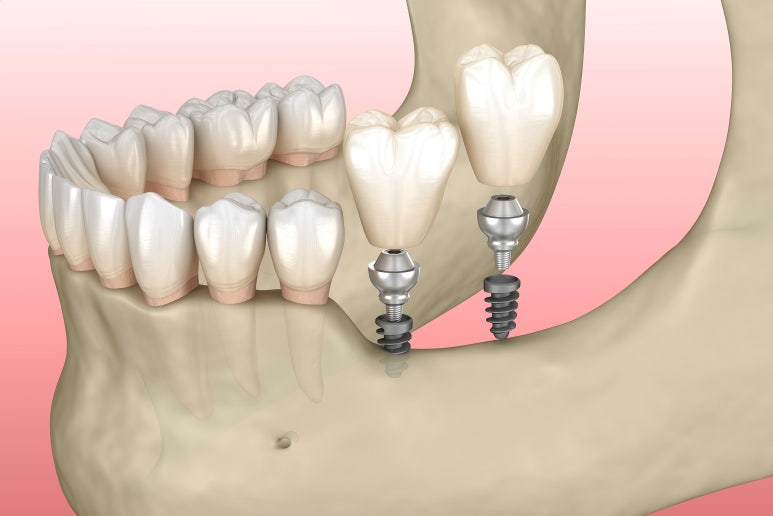

임플란트는 한국말로 인공치근, 다시 말해 가짜 뿌리입니다.

그래서 뿌리가 남아있을 때 하는 것이 아니라, 치아가 상실되었거나 완전히 뽑은 상태에서 진행하게 되는데요.

쉽게 설명해 드리면 잇몸 뼛속에 티타늄으로 된 나사 형태의 금속을 심는 것이 1차 수술이고요.

이후 금속 위에 최종 보철물을 얹는 것이 2차 수술입니다.

물론 상황에 따라 1차 수술과 2차 수술을 동시에 하는 경우도 있지만,

1차 수술 후 뼈 심은 나사가 완전히 달라붙을 때까지 덮어두었다가 2차 수술을 하는 경우가 일반적입니다.